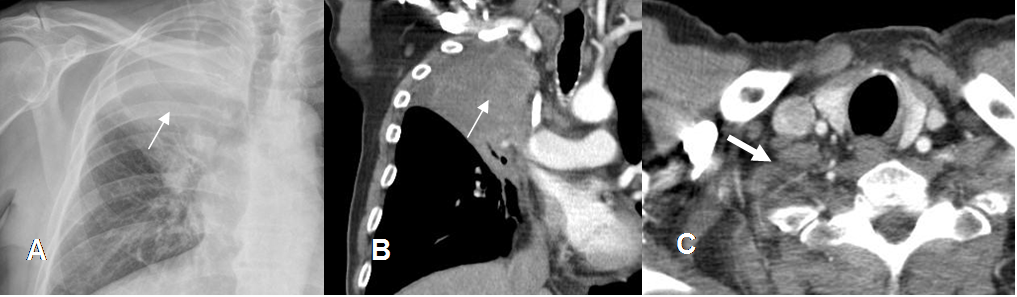

En todos los tumores malignos se encuentran lesiones hipointensas en T1 e hiperintensas en T2, que realzan con el contraste. Estos procesos producen efecto de masa o infiltran las raíces. (2). (Fig 14 y 15).

Fig 10. Neoplasia de pulmón.

A: Rx AP y B: TAC reconstrucción coronal. Tumor del surco superior, (Flechas delgadas) con extensión al espacio interescalénico y reemplazo de la grasa normal.

C: TAC axial. Adenopatías metastásicas que obliteran la grasa y engloban las raíces nerviosas.